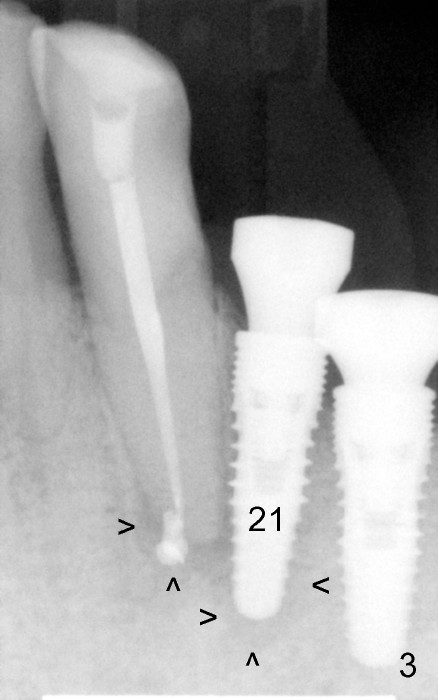

Three weeks post RCT for #22, the patient returns for implant placement at the sites of #19-21 (Fig.1,2). He is asymptomatic. But pain is not well controlled when osteotomy is being done at the site of 21. A shorter and smaller implant (4.1x12 mm, insertion torque <15 Ncm) is placed than planned (4.5x14 mm). One month postop, the implant is not stable at the site of 21 (Fig.3-5). There is a space around the implant, which is continuous with periapical radiolucency (Fig.3 arrowheads). It appears that the immediate implant should have been placed longer following RCT of the neighboring tooth. The tooth #21 has also pre-existing periapical infection.